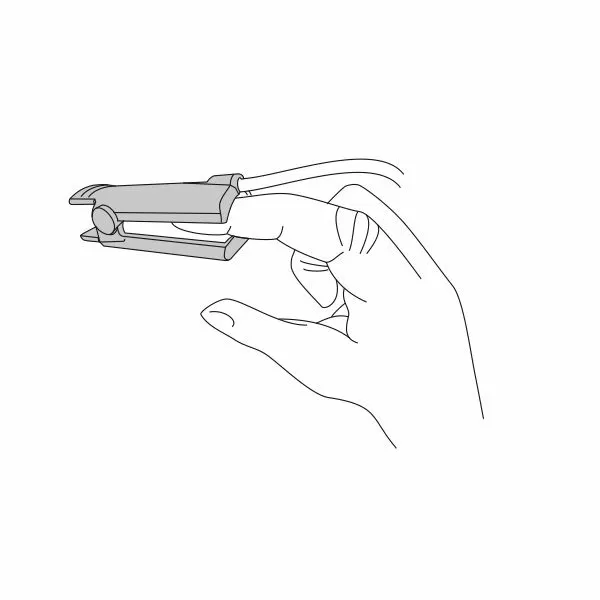

Почему может врать пульсоксиметр?

Причин, по которым пульсоксиметр может проводить измерения неверно, бывает несколько:

- у вас холодные руки. Согрейте их перед измерением;

- вы не до конца поместили палец внутрь прибора или измерению мешает длинный ноготь. Толстый слой гель-лака тоже может быть препятствием;

- вы долго находились в медицинской маске. Снимите ее, подышите глубоко и после этого делайте замер.